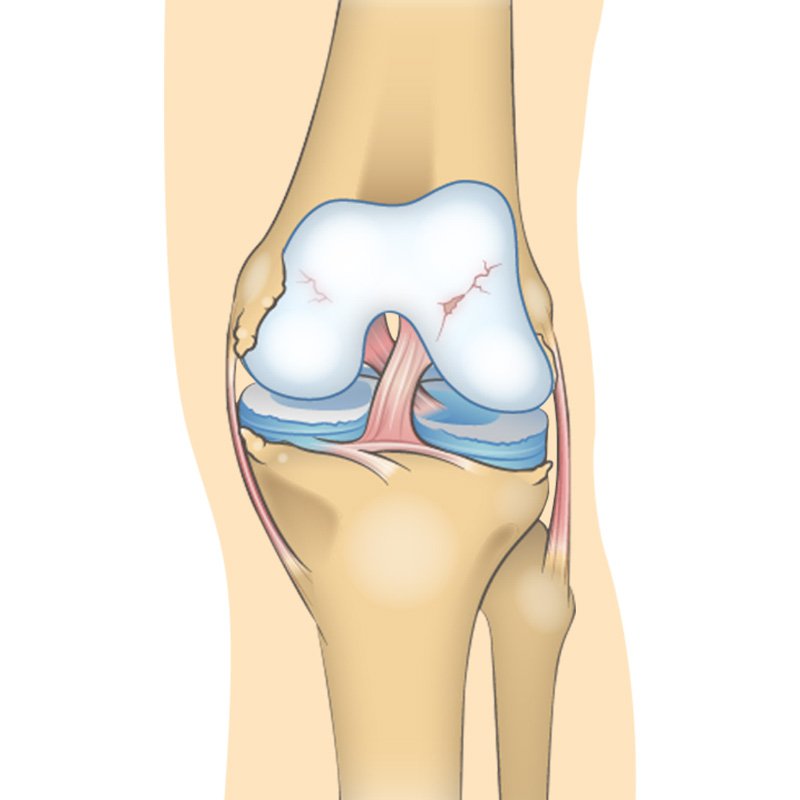

Over time osteoarthritis affects the bone cartilage and synovial fluid of the knee. With moderate knee OA, changes in the joint are much more evident the cartilage surface between the bones has begun to a road narrowing the gap between the femur and the tibia. hyaluronic acid which helps synovial fluid lubricate the joint is now becoming less viscous elastic and concentrated. Osteoarthritis often affects the sub-chondral bone Located just underneath the cartilage. Some contraband provides hydration and oxygen to the cartilage. Osteo fights may increase in number and size making the bone rougher. All these factors combined to make joint pain more severe and long-lasting both with movement and at rest. OA conditions worsened dramatically the joint spaces become far narrower causing more rapid and severe destruction of the cartilage in the knee becomes inflamed and sore. Synovial fluid is decreased increasing friction and pain during movement. Osteo fights continue to develop bone moves against bone not cartilage mobility activities of daily living and quality of life are severely impacted.”

This stage people will experience symptoms for the first time. They will have pain after a long day of walking and will sense a greater stiffness in the joint. It is a mild stage of the condition, The cartilage will likely remain at a healthy size.